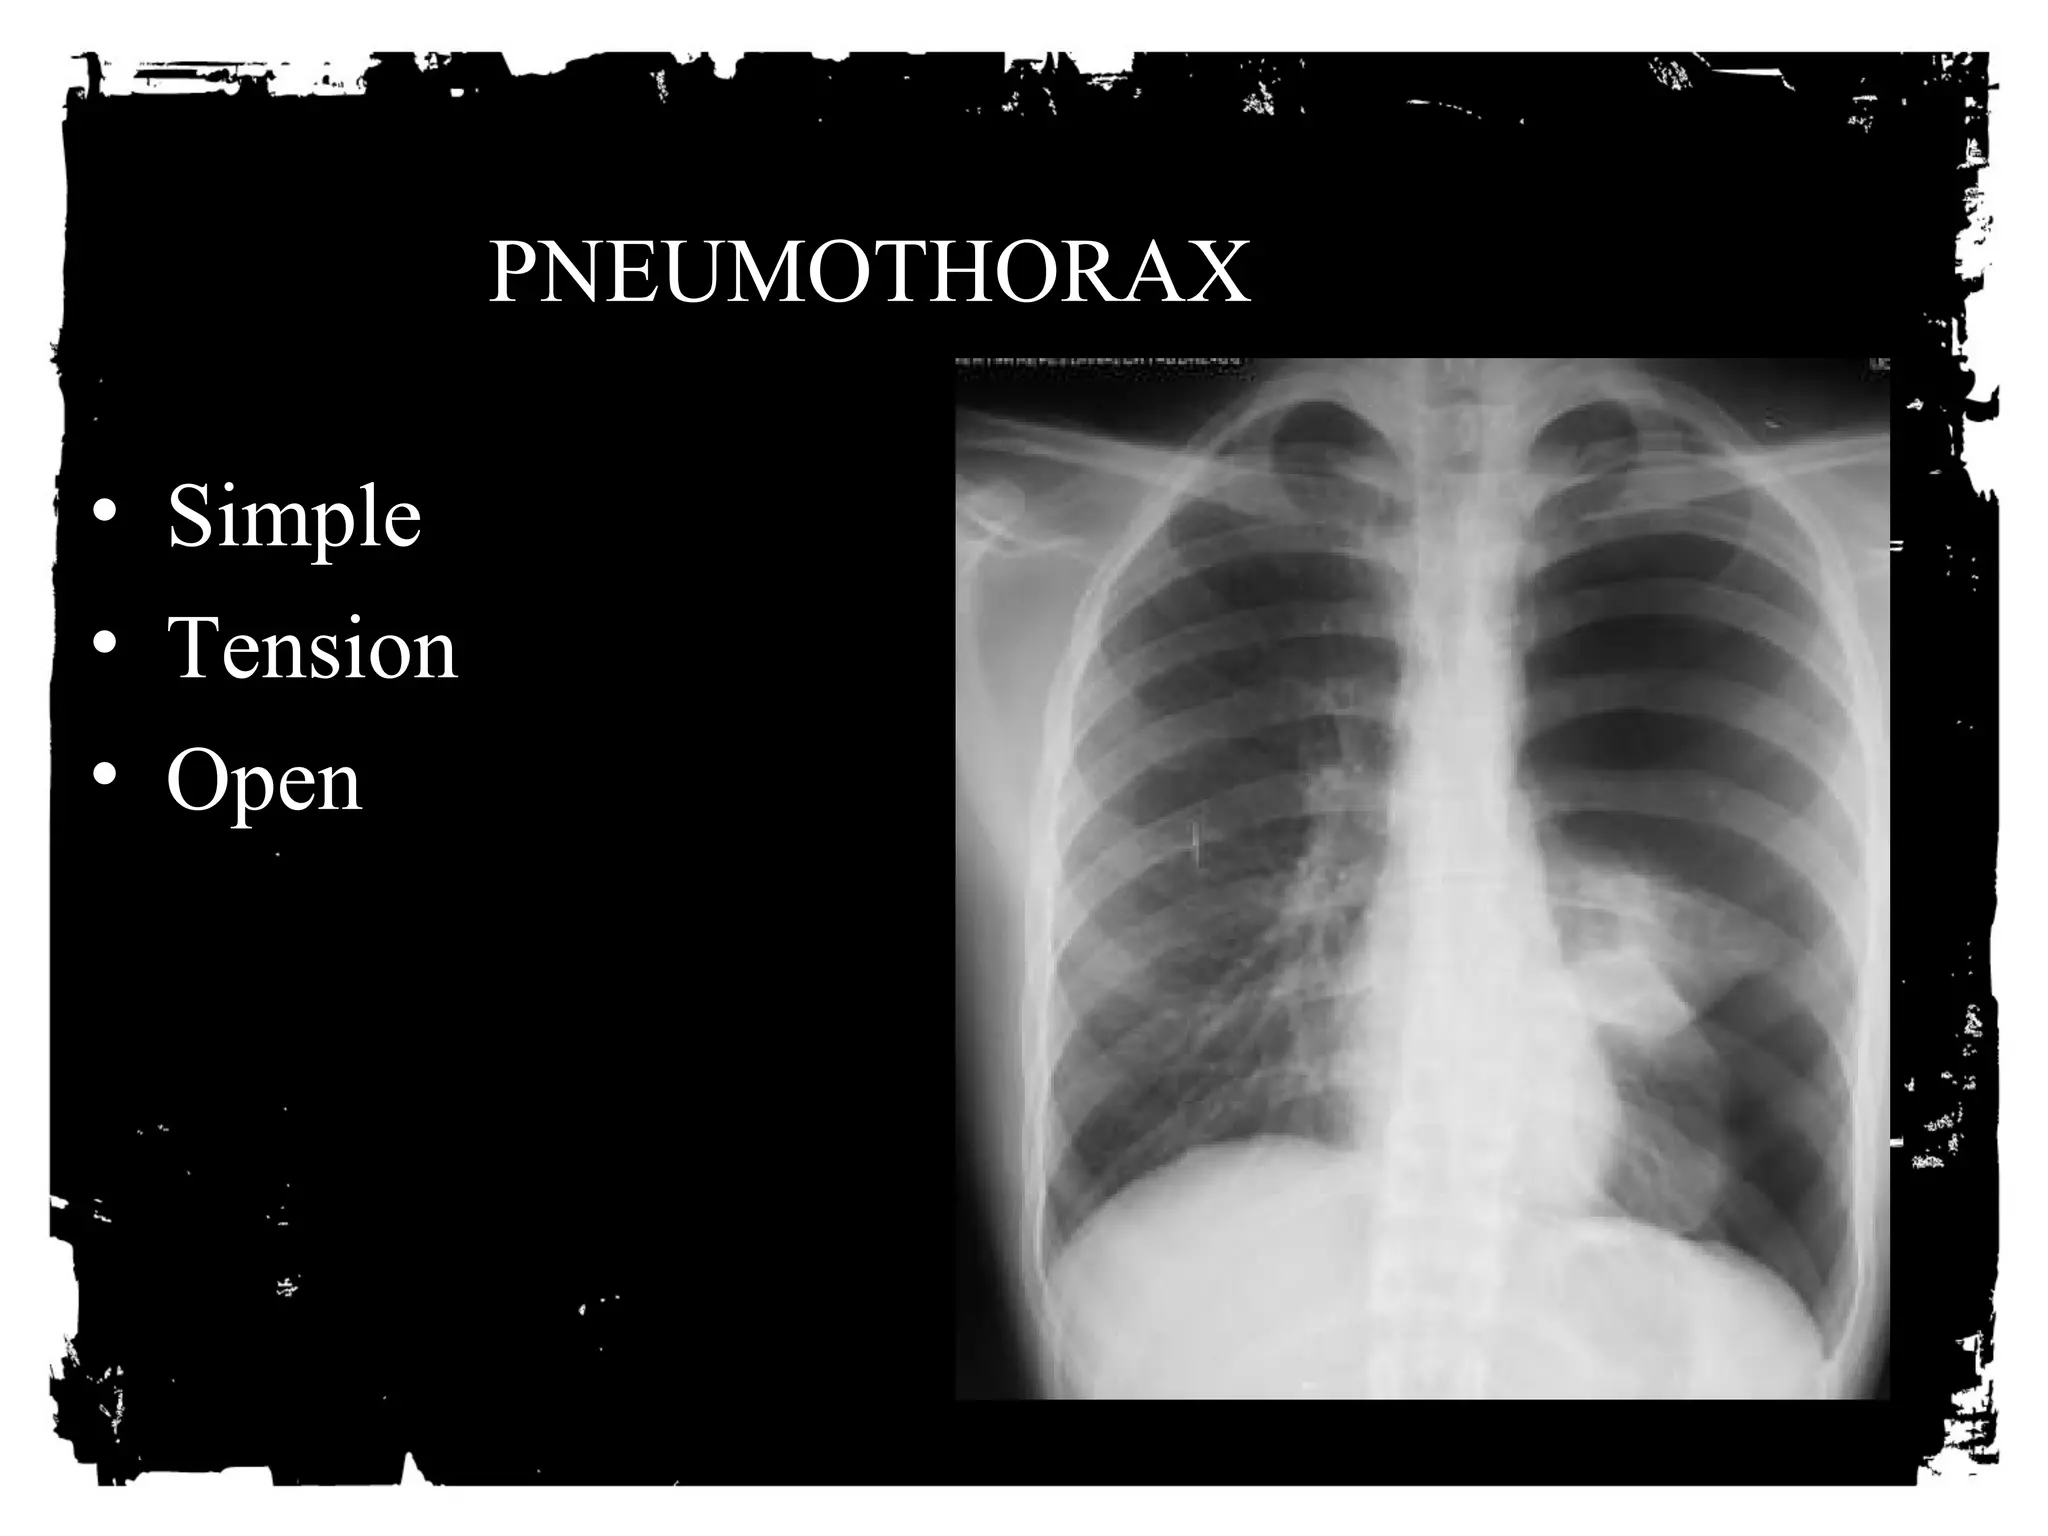

PNEUMOTHORAX

• Simple

• Tension

• Open

Pneumothorax: Simple

• Erect AP/PA view best

• Visceral pleural line

• No vessels or markings

• Variable degree of lung

collapse

• No shift

PNEUMOTHORAX: Tension

• Erect AP/PA view best.

• Shift of mediastinum away

from PTX side.

• Depressed hemidiaphragm.

• Degree of lung collapse is

variable.

PNEUMOTHORAX:

Diagnostic limitations of supine view

Supine AP view has limited sensitivity: 50%.

Deep sulcus sign.

Too sharp heart border/hemidiaphragm sign.

Increased lucency over lower chest.

Subpulmonic air sign.

Can see vessels.